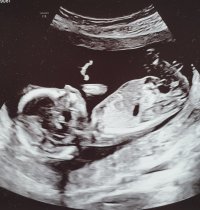

Er du gravid igjen? Sååå kjektNoen som ser noe her? 12+6![]()

Hun er såå spent på kjønnet og spurte om jeg ville legge ut ser ut som jenteNoen som ser noe her? 12+6![]()

JenteNoen som vil gjette her? uke 13+1Vis vedlegget 472328

Tipper også jenteNoen som vil gjette her? uke 13+1Vis vedlegget 472328